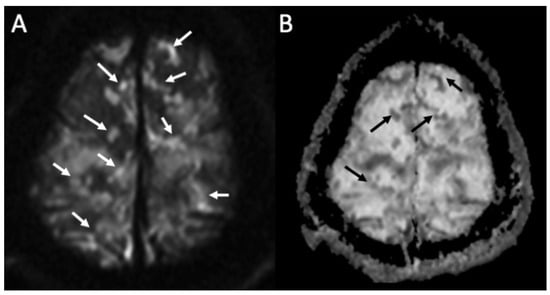

| Candida albicans | • Microabscesses • Vascular lesions |

| Aspergillus fumigatus | • Abscesses • Vascular lesions |

| Herpes Virus type 1 | • Mesio-temporal involvement • Bilateral and asymmetric pattern • Cortical hyperintensity on T2 and FLAIR, with restricted diffusion (acute phase) and cortical enhancement (subacute phase) • Hemorrhagic foci |